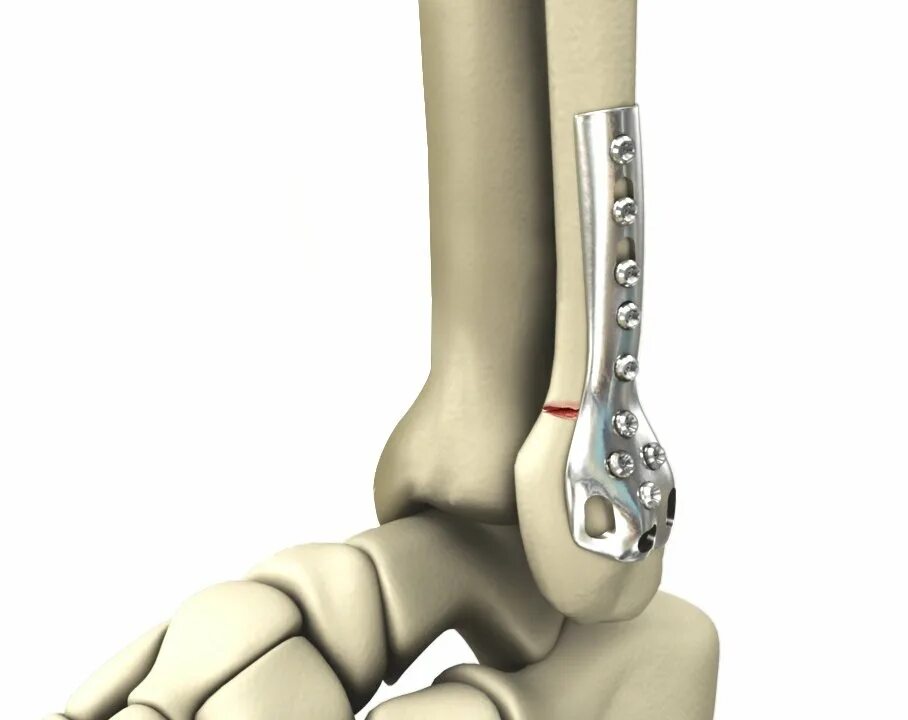

После остеосинтеза лодыжек